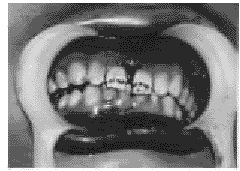

为分界左侧上颌骨向下移位,左侧上、下颌前牙咬合早接触,

图2 以

为分界左侧上颌骨向下移位,左侧上、下颌前牙咬合早接触